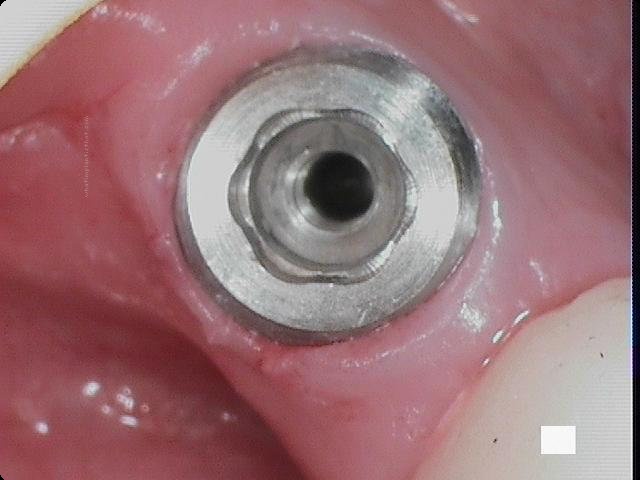

Additional Features

CollarCurved apexFlared flangeReverse buttress